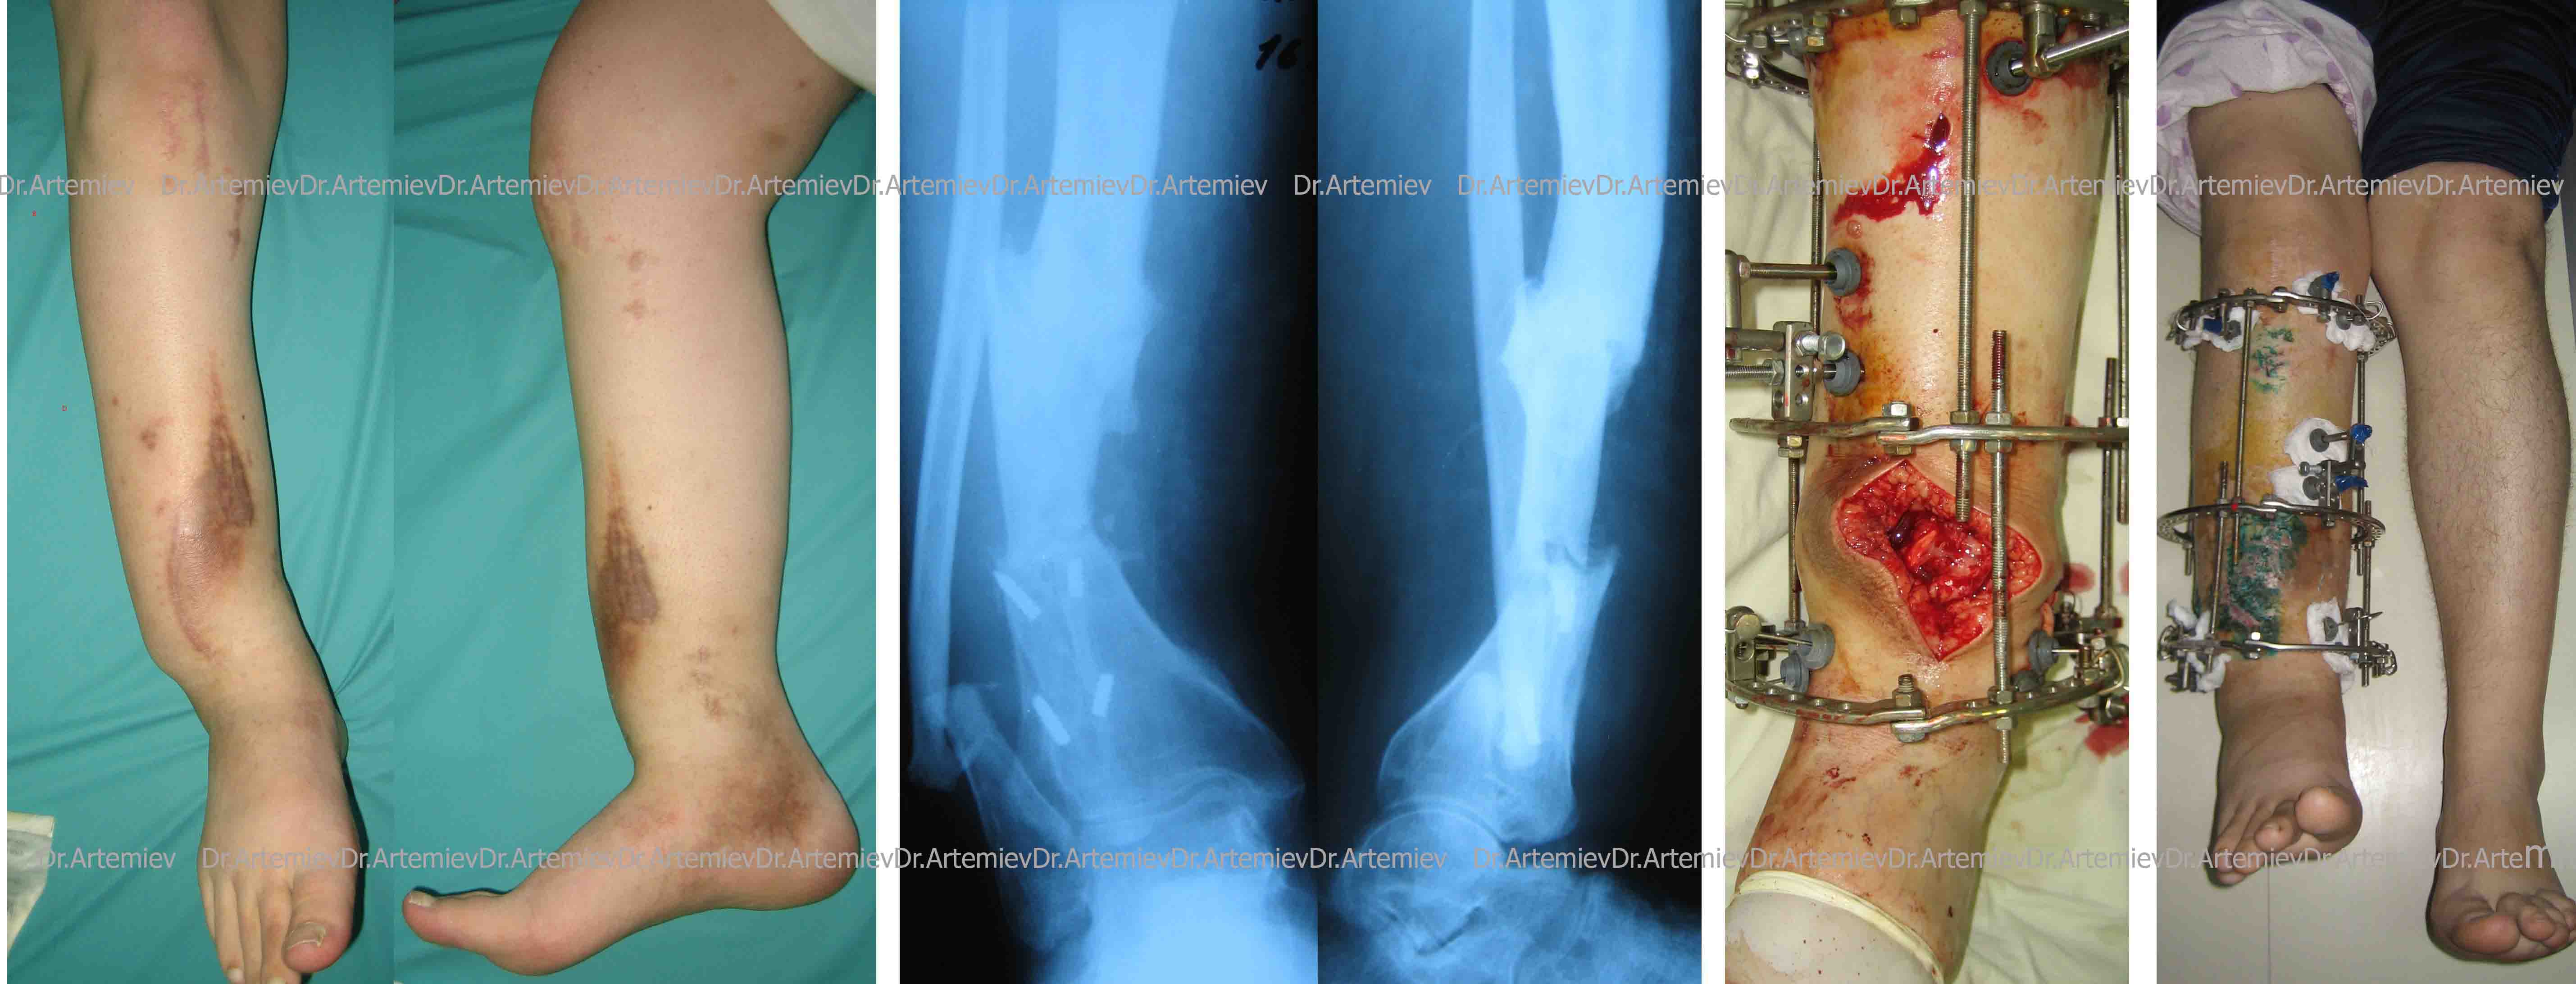

Месяца три назад наш коллега представлял одного больного с ложным суставом голени. Сложный анамнез - 10 лет лечения, 2 БИОСа (о чем говорят сломанные винты) и пр...

Я в итоге его прооперировал, сейчас он уже удлинил голень на величину имеющегося укорочения - 5 см.

Последние снимки будут на следующей неделе, а пока - то, что есть - во вложении.